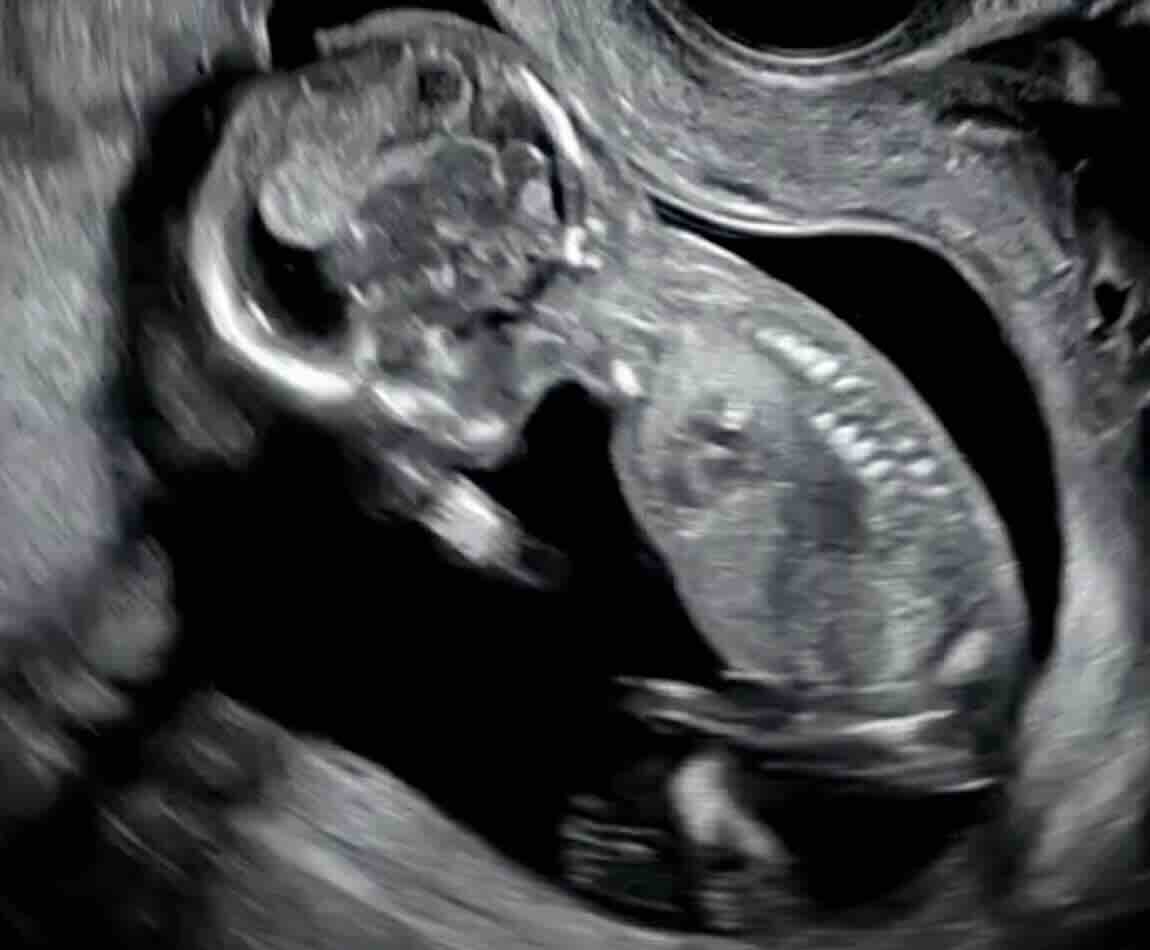

7. Hafta

Embriyo net görülür (ortalama 10 mm).

Kalp atışı pozitif olmalıdır (dakikada 100-120 atım).

Düşük belirtisi: Kalp atışının olmaması, embriyonun beklenenden küçük olması.

Cevap: Bazen yumurtlama geç olabilir. Doktorunuz bir hafta sonra tekrar ultrason isteyebilir. Hâlâ yoksa düşük tanısı konur.

8. Hafta

Embriyo artık bebek görünümüne yaklaşır (15-20 mm).

Kalp atışı dakikada 140-160 civarında olmalıdır.

Düşük belirtisi: Kalp atışının durması, gelişimin durması.

Cevap: Kanama, ağrı ve ultrasonda bebeğin kalp atışının olmaması veya ölçülerinin geri kalması.